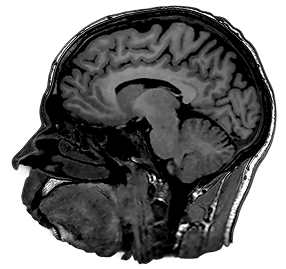

3D T1

1.5T

3D MPRAGE

1.0 x 1.0 x 1.0mm

5:45

0.5T

3D SPGR

1.1 x 1.1 x 1.1mm

5:30